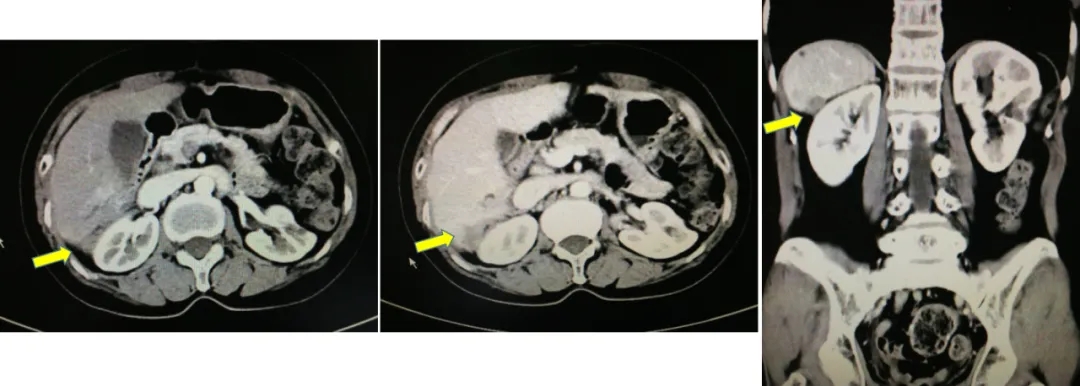

2014.6.11 CT:脾周囊性低密度灶2.4*2.7cm,较2014.2.26增大,腹主动脉旁肿大淋巴结,考虑“卵巢癌复发”。

CT检查结果